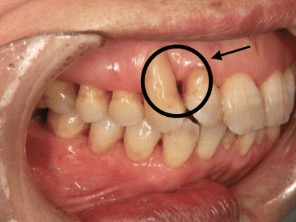

①歯周病による歯根露出

歯周病で歯槽骨が吸収されていくと歯肉が後退する(歯茎が下がる)ように歯根の象牙質が露出する事で終わります。